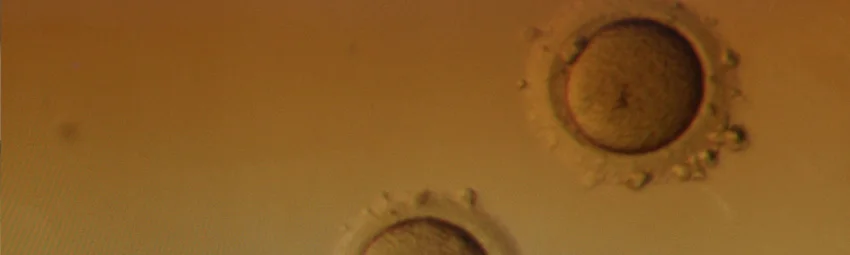

Криоконсервация – это вспомогательная репродуктивная технология, которая подразумевает заморозку яйцеклеток в жидком азоте. Изначально замораживались нативные (ничем не обработанные) яйцеклетки, но такая технология имела ряд недостатков. Из-за образования кристаллов льда внутри клеток они повреждались и становились нежизнеспособными. Поэтому после разморозки для последующего оплодотворения можно было использовать около 50-70% клеток.

В настоящее время используется более современная технология, которая называется витрификация или ультрабыстрая заморозка. В этом случае биоматериал сначала помещается в специальную среду – криопротектор. Эта среза позволяет избежать образования кристаллов льда и при этом моментально заморозить яйцеклетки. За счет этой особенности «выживаемость» яйцеклеток повышается до 98%, при этом их можно хранить практически неограниченное время.